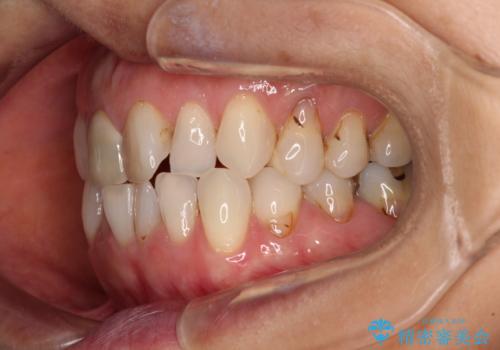

- 前歯のデコボコと口を開けたときに見える銀歯を気にして来院された患者様です。

ある程度デコボコが解消されれば大丈夫とのことで、インビザライン・モデレートパッケージを利用して歯列を整えて行くこととしました。

矯正治療後に銀歯をセラミッククラウンなどに置き換えていくと、どうしても後戻りを起こしてしまうため、矯正治療が概ね終了した時点で銀歯を全てセラミックとし、最後に仕上げでインビザラインにを用いて細かいデコボコを改善していくこととしました。